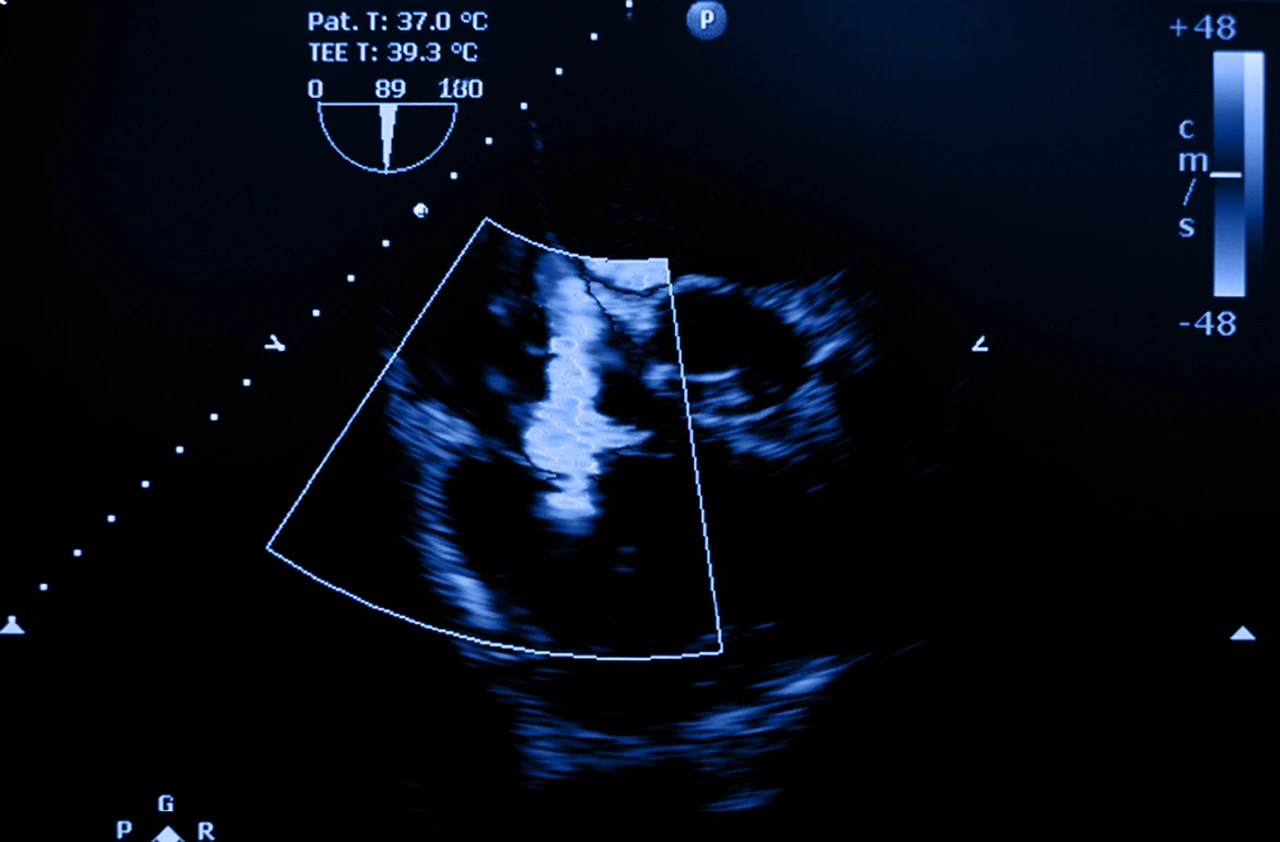

Ecocardiograma para identificar la presencia de insuficiencia tricúspidea por regurgitación de la válvula tricuspídea.

Como pruebas complementarias se pueden indicar ecocardiogramas que se considera la principal herramienta para confirmar la regurgitación tricuspídea y evaluar su severidad. Adicionalmente se puede emplear electrocardiograma, radiografía de tórax y resonancia magnética cardíaca para valorar el tamaño y la función del ventrículo derecho, así como el impacto de la enfermedad en la circulación pulmonar y sistémica.